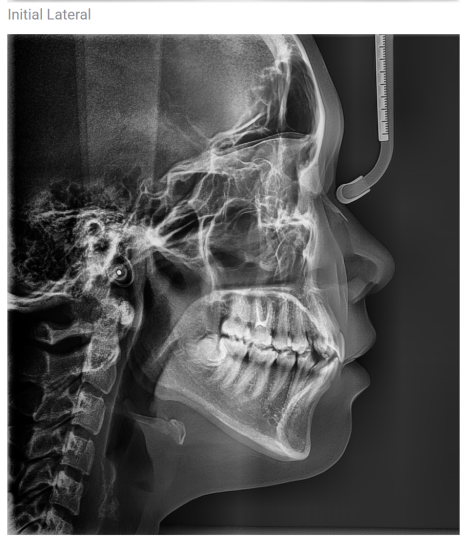

It is essential to make a diagnosis that also looks at the overall facial proportions and tooth alignment through CT scans and dental cast analysis.